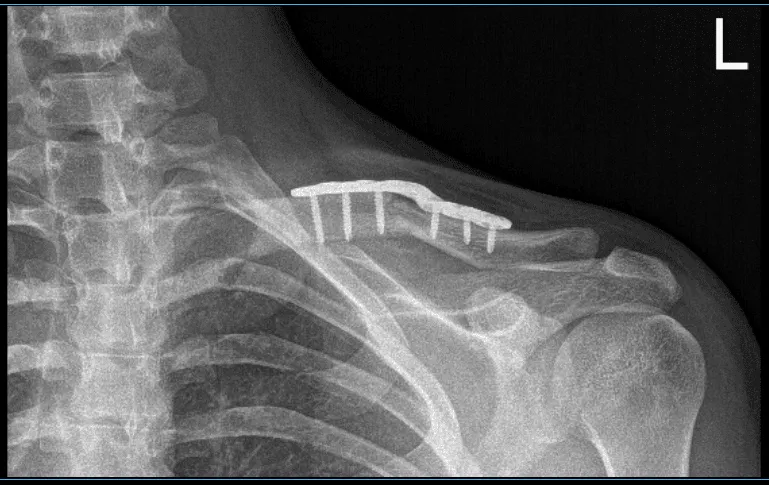

Con una disección aguda y contundente, se alcanzó y expuso el hueso y el lugar de la fractura. El lugar de la fractura fue abierto, lavado y limpiado con curette. La fractura se redujo y se colocó una placa superior. La placa se fijó proximal y medialmente con dos tornillos para el proceso de retención para la compresión.

Finalmente, se colocó la placa y se realizó la compresión usando un tornillo de compresión. Se usaban dos tornillos no bloqueantes g y uno de bloqueo a cada lado. Se tomaron las imágenes finales y se consideraron satisfactorias. Se guardaron las imágenes finales.

Resultados de la radiografía de 4 semanas de la clavícula izquierda tras la cirugía